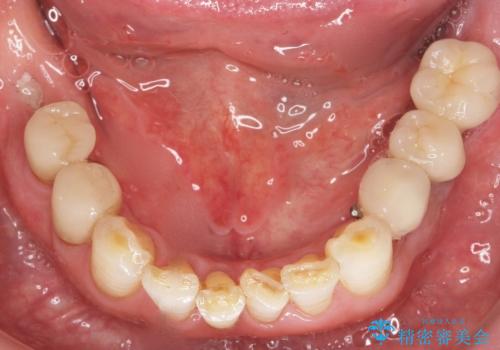

奥歯のインプラント 70代男性

- 奥歯の違和感を主訴に来院された患者様です。

精査したところ、右下の奥歯は大きなう蝕により保存不可能な状態でした。

患者様のご希望により、抜歯後インプラント治療を行いました。

奥歯でしっかりと咬むことができるようになり、大変喜んで頂けました。